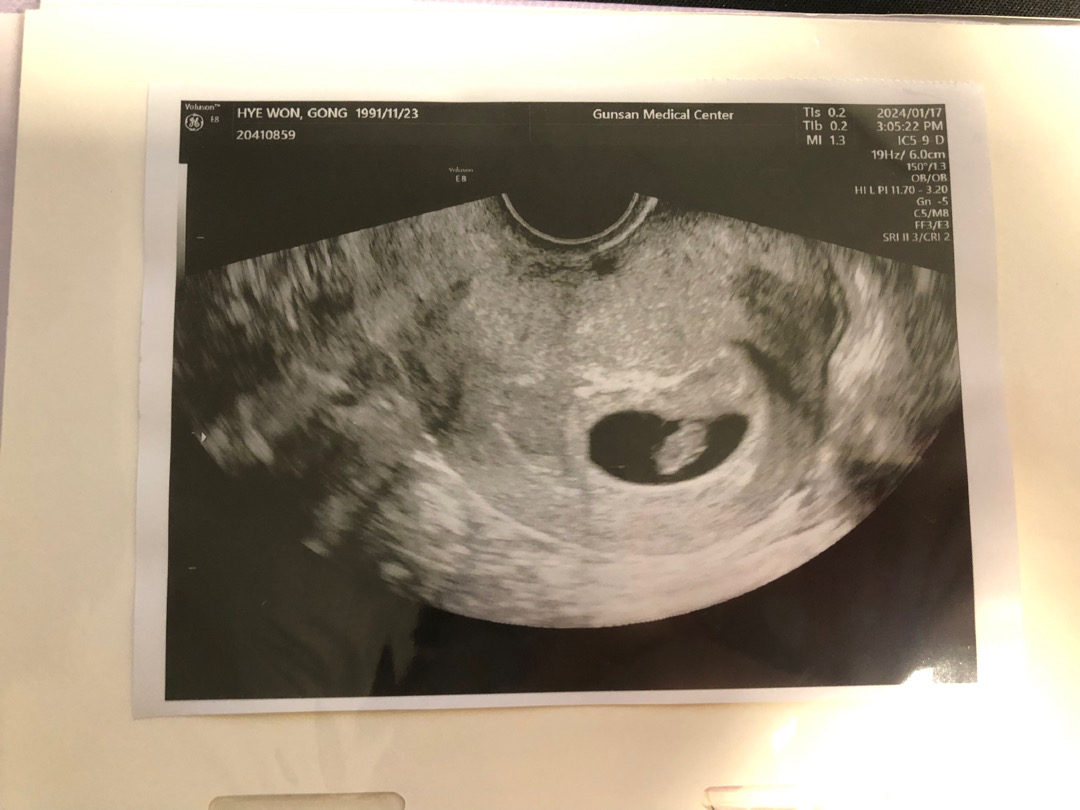

6주 6일 심장소리 듣고 왔어요 ㅎㅎ

일주일동안 갈생냉이 쪼금씩 나왔어서 걱정됐는데 다행이 아무이상도 없구 심장소리도 잘 듣고 왔어요 ㅎㅎㅎ 다른 6,7주차 초음파사진들에 비해 아기집이 좀 커보이는 것 같은데 아기 크기도 정상이고 아기집에 대해선 아무말씀 없으셨어용 2주 뒤에 보면 팔다리도 잘 보이지 않을까 기대하고 있어요 ㅎㅎ